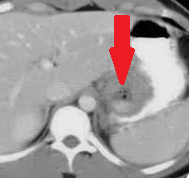

Contrast-enhanced CT of the abdomen, revealing air in intrahepatic biliary tree (pneumobilia) (red arrow)